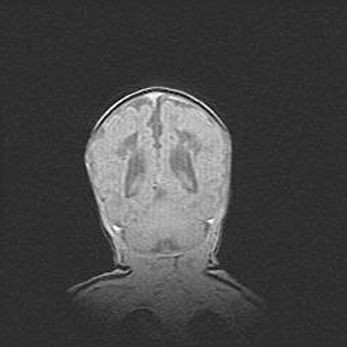

Церебральная ишемия II.

Возраст: 5 дней

Вес: 3400 г

Пол: женский

Окружность головы: 35 см

Срок гестации: 39 недель

Церебральная ишемия – это заболевание, характеризующееся недостаточностью (гипоксией) либо полным прекращением (аноксией) снабжения мозга кислородом по причине закупорки одного или нескольких сосудов. Это приводит к  что метаболическим расстройствам различной степени тяжести в тканях головного мозга, развитию коагуляционных некрозов и гибели нейронов.